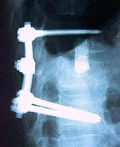

Wirbelsäulenimplantat und Tools für die

Wirbelfusion als hochpräzise minimalinvasive chirurgische

Tools